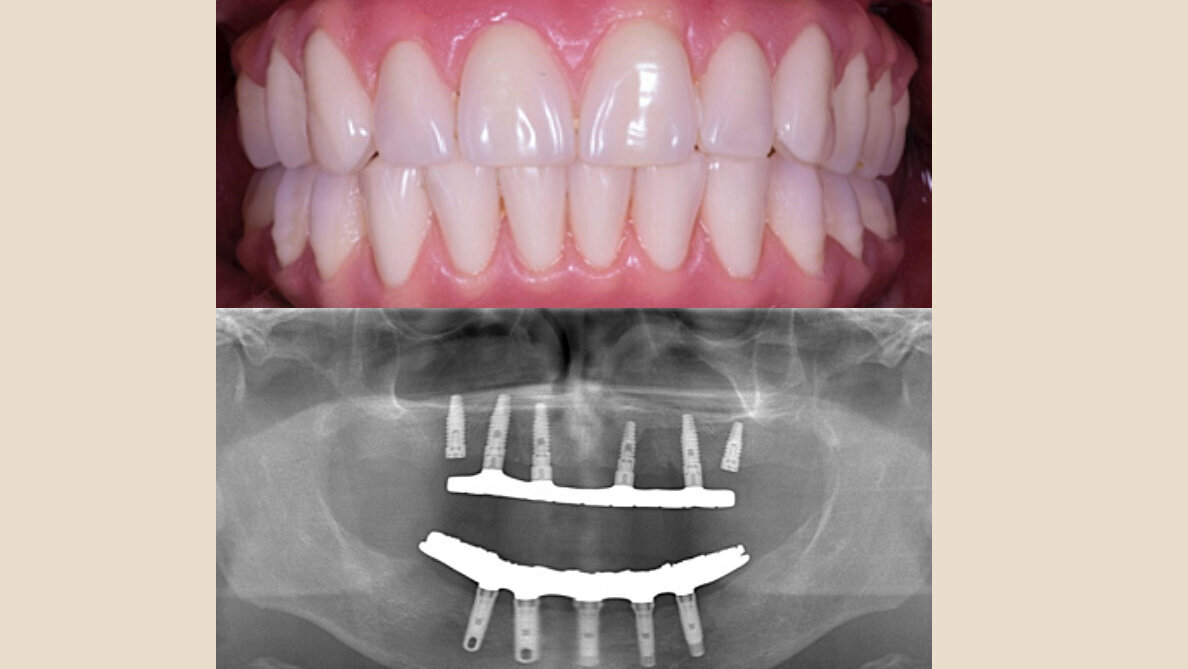

Paciente masculino de 56 años a quien se le colocaron 5 implantes dentales y Prótesis Híbrida Mandibular inmediata en 2012. Seguimiento del caso hasta 2019.

Diez pacientes a los cuales se les colocaron de cuatro a cinco implantes dentales en la mandíbula anterior y restaurados en 3 a 8 días con la Prótesis Híbrida Fijo-Removible Final, que fue fabricada utilizando la barra de DuralayÒ de OSU (Ohio State University)5. Se describen el protocolo quirúrgico y la técnica de la carga inmediata de los implantes.